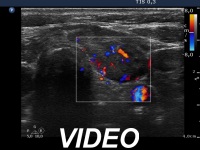

Ultrasonography. Both lobes were hypoechogenic and contained several hypoechogenic areas do not corresponding to nodules. The echogenicity index was 20%. The vascularization was a bit increased.

Aspiration cytology was performed from one of the hypoechogenic areas in the right thyroid and resulted in benign, hormonal atypia.